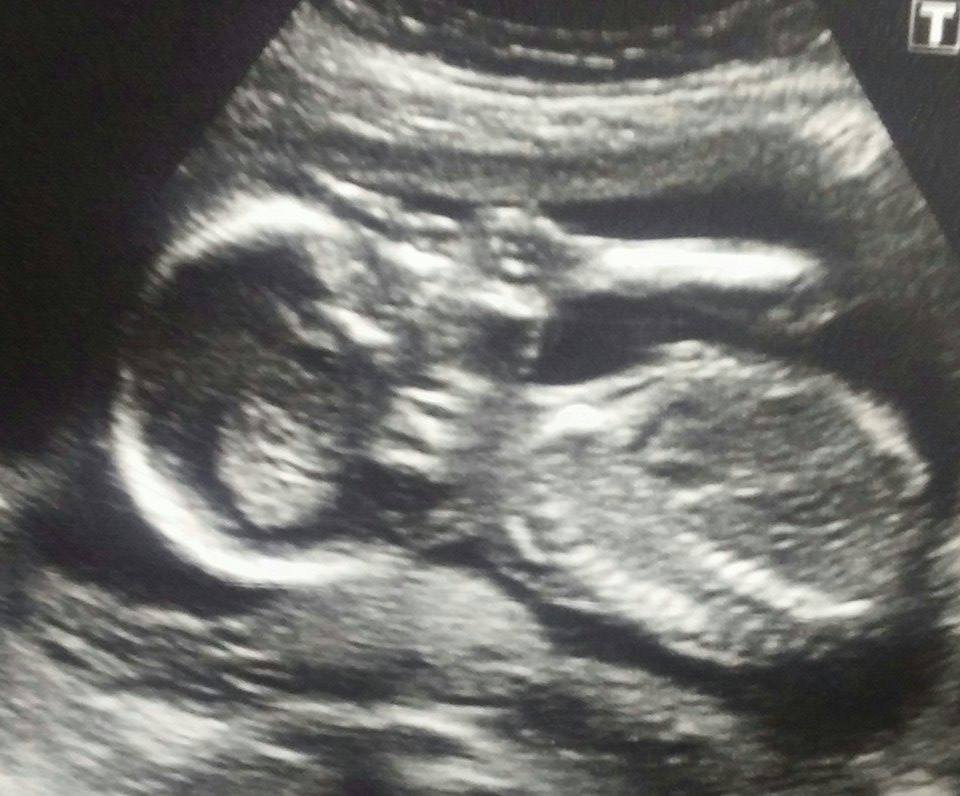

BOY! Had girl name picked out and everything but it's definitely a little boy! Such a cutie, and moving and kicking like crazy! =D>

Here he is!! Such a hyper and active guy. Future soccer player like daddy!